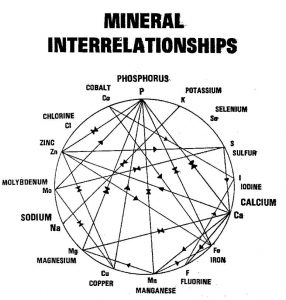

These two pictures show the relationship between the different elements and how an imbalance in one can be corrected by using its companion or its antagonist.

These two pictures show the relationship between the different elements and how an imbalance in one can be corrected by using its companion or its antagonist.